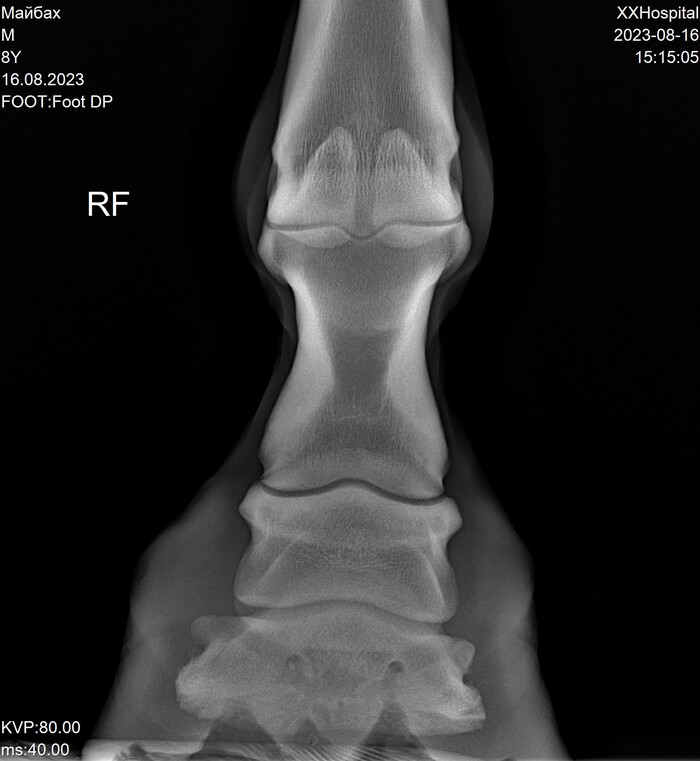

Пока лента далеко не убежала и есть возможность сравнить с идеальными снимками Майбаха (см. предыдущий мой пост , там комментировать нечего, всё круто).

На этих x-ray снимках Домбай.